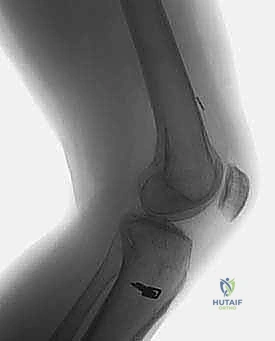

* الأشعة السينية (X-rays): ضرورية لتقييم اتساع الأنفاق العظمية السابقة (Tunnel Widening)، مواقع مسامير التثبيت القديمة، ووجود أي علامات لخشونة المفصل أو انحراف محوري.

* الأشعة المقطعية (CT Scan): في حالات الفشل الجراحي، تعتبر الأشعة المقطعية السلاح الأهم. فهي توفر نمذجة ثلاثية الأبعاد (3D) دقيقة جداً لمواقع الأنفاق العظمية القديمة وحجمها، مما يساعد الدكتور هطيف في اتخاذ قرار حاسم: هل يمكن حفر أنفاق جديدة فوراً، أم يجب إجراء الجراحة على مرحلتين؟

بناءً على الأشعة المقطعية (CT Scan)، يحدد الدكتور هطيف مسار الجراحة: